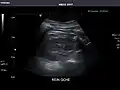

Abdominal Ultrasound (Full Exam)

STRUCTURED REPORT

(Technique: Transabdominal ultrasonography; Device: Toshiba Aplio XG)

Kidneys: Right and left kidneys measure 11.5 cm and 12 cm in length respectively. No hydronephrosis. Small left lower pole kidney cyst.

Right kidney -